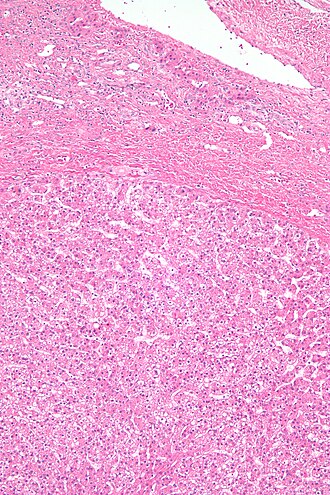

Hepatic adenoma. H&E stain. | |

| LM | sheets or cords of cells with mild variation of cell and nuclear size; cords of cells up to 3 cells thick, vascular (large arteries, dilated thin-walled veins), +/-cytoplasmic clearing/pale (due to glycogen); negatives: no bile ducts, no portal tracts, no cirrhosis |

- Sheets or cords of cells with mild variation of cell and nuclear size.[4]

- Cords of cells up to 3 cells thick.[5]

- Cells may have cytoplasmic clearing due to glycogen or be pale - obvious if seen.

- Vascular - large arteries, dilated thin-walled veins.

Negatives:

- No bile ducts.

- No portal tracts.

- No cirrhosis! If cirrhosis is present it isn't a hepatic adenoma - important.